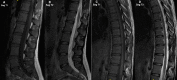

Methods: All climbers of the Swedish national sport climbing team (n = 8), and individuals having trained for selection to the national team (n = 11), were prospectively included. A control group, matched in age and sex, were recruited. All participants underwent a thoracolumbar MRI (1.5 T, T1- and T2-weighted imaging), evaluated according to Pfirrmann classification, modified Endplate defect score, Modic changes, apophyseal injuries and spondylolisthesis. Pfirrmann ≥ 3, Endplate defect score ≥ 2 and Modic ≥ 1 was defined as degenerative findings.

Results: Fifteen individuals, 8 women, participated in both the climbing group (mean age 23.1, SD 3.2 years) and the control group respectively (mean age 24.3, SD 1.5 years). In the climbing group, 6.1% of the thoracic and 10.6% of the lumbar intervertebral discs showed signs of degeneration according to Pfirrmann. One disc with a grade above 3 was present. Modic changes in the thoracic/lumbar spine were prevalent in 1.7%/1.3% of the vertebrae. Degenerative endplate changes according to the Endplate defect score were found in 8.9% and 6.6% of the thoracic and lumbar spinal segments of the climbing group, respectively. Two apophyseal injuries were found, while no participants displayed signs of spondylolisthesis. There was no difference in point-prevalence of radiographic spinal changes between climbers and controls (0.07 < p < 1.0).